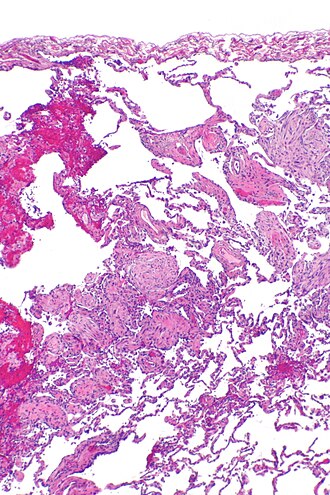

Organizing pneumonia. H&E stain. | |

| LM | distal airway disease -- airways plugged with organizing exudate (fluffy light-staining paucicellular regions with stellate cells); no hobnailing of pneumocytes; type 2 pneumocytes hyperplasia is absent |

- Distal airway disease -- airways plugged with organizing exudate ("Masson bodies").

- "Organized exudate" = fluffy light-staining paucicellular regions with stellate cells (fibroblasts & immature connective tissue).

- No hobnailing of pneumocytes.

- Type 2 pneumocytes hyperplasia is absent.